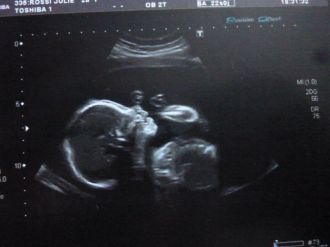

2 eme Echo

La meilleure de toute, tout va bien elle etait tranquille les jambes croisées c'etait trop drole.

Apparrament toutes les mesures sont bonnes, vivement qu'elle soit dans mes bras, encore quelques mois a attendre !!!!

Message déposé le 23.11.2011 à 17:59